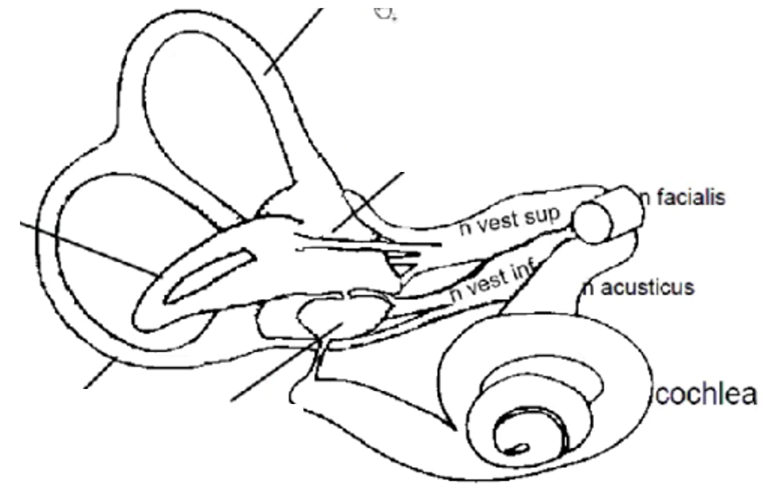

- SCC – semi cirkular canal (båggång)

Vad ansvara de olika delarna för?

- SCC – semi cirkular canal (båggång)

- Anterior (rörelser framåt snett)

- Posterior (rörelser bakåt snett)

- Lateral (huvud fram och tillbaka horisontalt)

- Cochlea ger info till n. acusticus

- Balanssystem består av tre båggångar som ger information till

- övre vestibularisnerv – anterior scc, lateral scc och utriculus

- nedre vestibularisnerv – posterior scc och sacculus

- Ovan tre nerver går ihop till n. vestibulocochlearis och sällskapar sen med n. fascialis

- Kraftningar, lutningar och accelerationer - huvudets position i förhållande till gravitation

- Utriculus

- Sacculus

Temporal fraktur kan ge problem med vad med tanke på vilke nerver som löper där?

Balans (vestibulär del), hörsel och muskler i ansikte

Vad ansvarar för kraftningar, lutningar och accelerationer - huvudets position i förhållande till gravitation

Utriculus och Sacculus